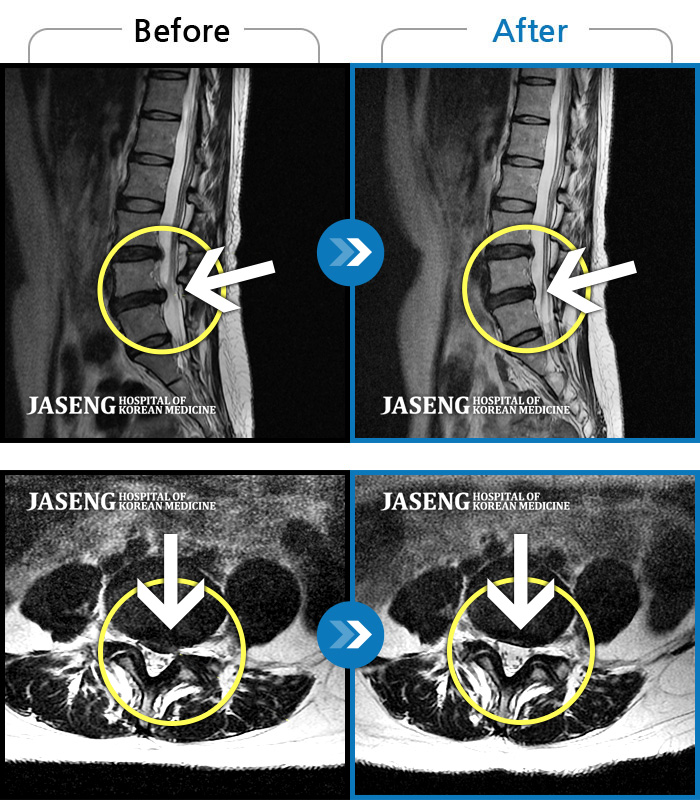

허리 골반 통증이 있고 다리가 저리고 아파 걷기가 힘들다.

2025.02.10 ~ 2025.09.13